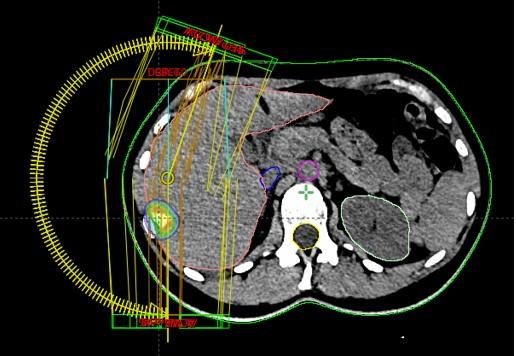

Bolesnica, rođena 1958. Dijagnoza: Adenocarcinoma lobi inferioris pulmonis sinistri